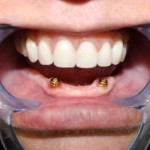

Este é um caso mais simples de se fazer e com um valor (custo-benefício) bastante cómodo.São somente 4 implantes na arcada inferior suportando uma barra sobre a qual será transferido em parte o esforço mastigatório. É confeccionada em RESINA como uma prótese total convencional.